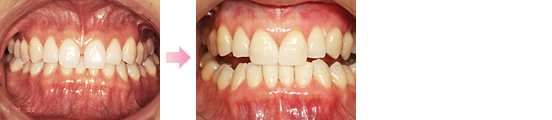

症例1 ・・・約10年間ほとんど変化ありません。